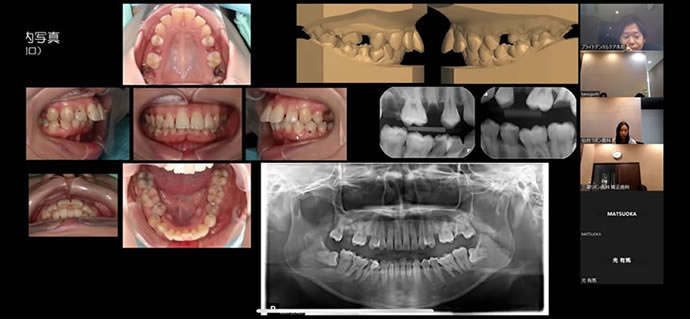

当グループ歯科では口腔内や顔貌を含めた精密な検査を行い、多くの歯科医師による診断と治療方針の検討会を行っております。

今回はどうして歯を失ってしまうようになったかということに関する原因を分析して意見を出し合い、診断・治療方針を行うような内容となっていました。